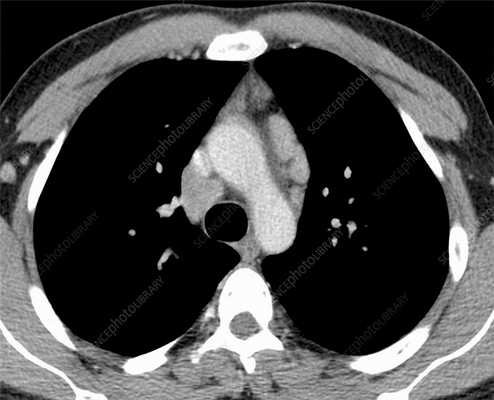

КТ ОГК. Объемное образование в средостении (патологически измененный лимфоузел), подтвержденная лимфома.

Лимфомы медиастинальной локализации не всегда диагностируются при рентгенологическом обследовании. Компьютерная томография, более детально, чем обзорная рентгенография позволяет рассмотреть конгломерат опухоли, увеличение лимфоузлов средостения, вовлечение паратрахеальных, трахеобронхиальных, прикорневых лимфатических узлов. Диагностическая значимость магнитно-резонансной томографии в верификации лимфом средостения признается не всеми авторами.